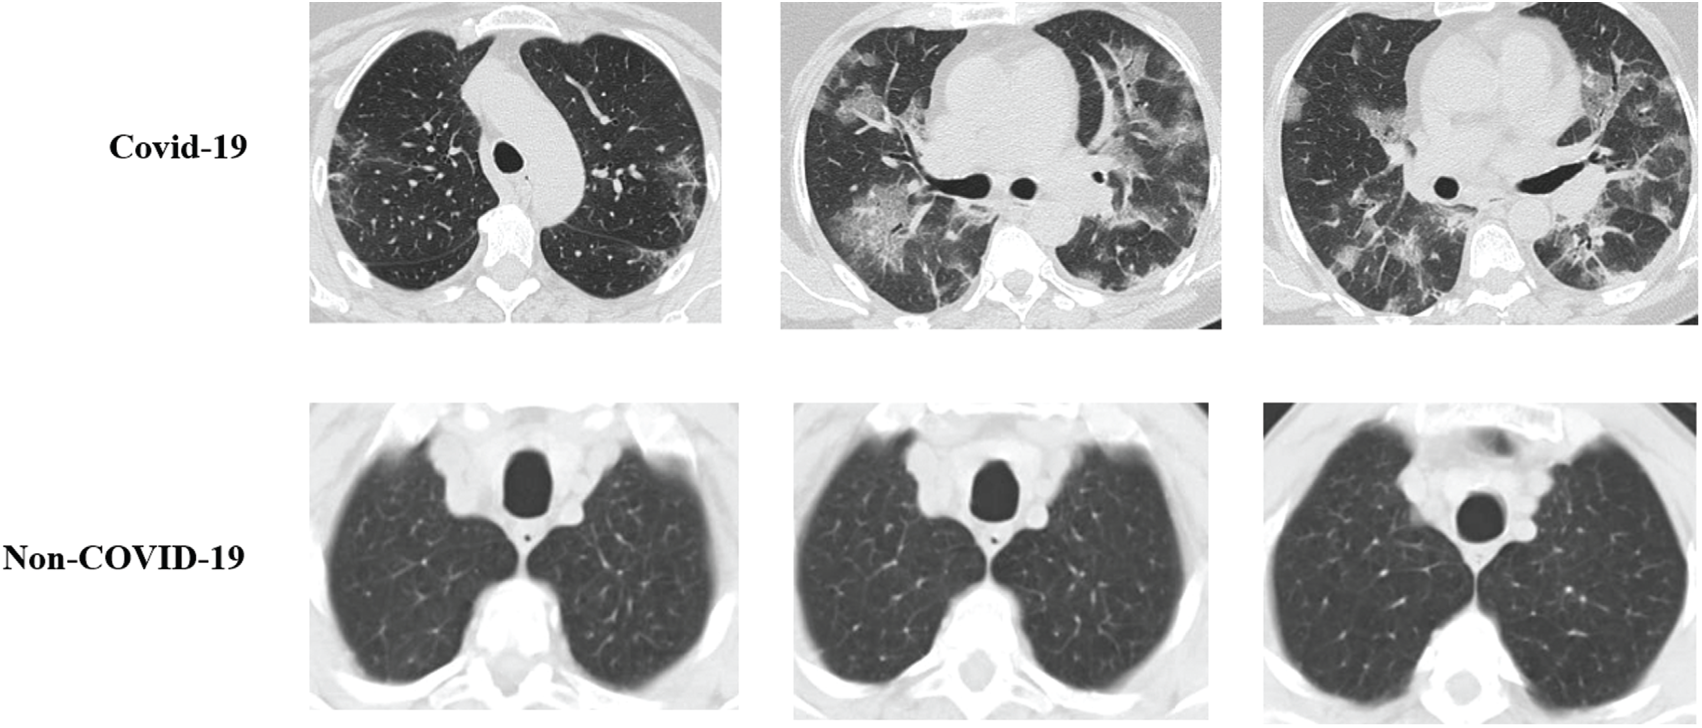

The performance of the proposed methodology was evaluated and justified in this section. The proposed methodology was validated by considering statistical measurements such as accuracy, precision, recall, sensitivity, specificity, and F_Measure. The proposed methodology was compared with existing methods such as CNN-EPO, and CNN-FA. The proposed method was tested using COVID-19 CT scan image database that consists of 2,482 images. The database containing the CT images has two folders such as COVID-19 and non-COVID-19 respectively. The database consists of 1,252 COVID-19 positive images and 1230 non-COVID-19 images. Among the images, 1865 images were utilized for testing whereas the remaining was used for training the proposed classifier. The implementation parameters of the proposed method are presented in Tab. 1. The performance metrics of the statistical measurements are presented in this section. A set of sample CT images is shown in Fig. 3.

Figure 3: Sample CT images of COVID-19 and non-COVID-19

The proposed method was validated using the collected CT scan images. CT scan images from COVID-19 patients were sourced from the literature [25]. In this database, a total of 1252 CT images that are positive for COVID-19 and 1230 CT images of patients who are not infected by SARS-CoV-2, 2482 CT is present. This information was collected on a real-time basis from patients admitted in medical clinics from Sao Paulo, Brazil. The aim of this research work is to stimulate an innovative artificial intelligence technique that can distinguish a person as either COVID-19 positive or negative by examining his/her CT scan image. The collected CT scan images were utilized to validate the performance of the proposed methodology. Sample images of COVID-19 positive cases and non-COVID-19 are illustrated in Fig. 3.